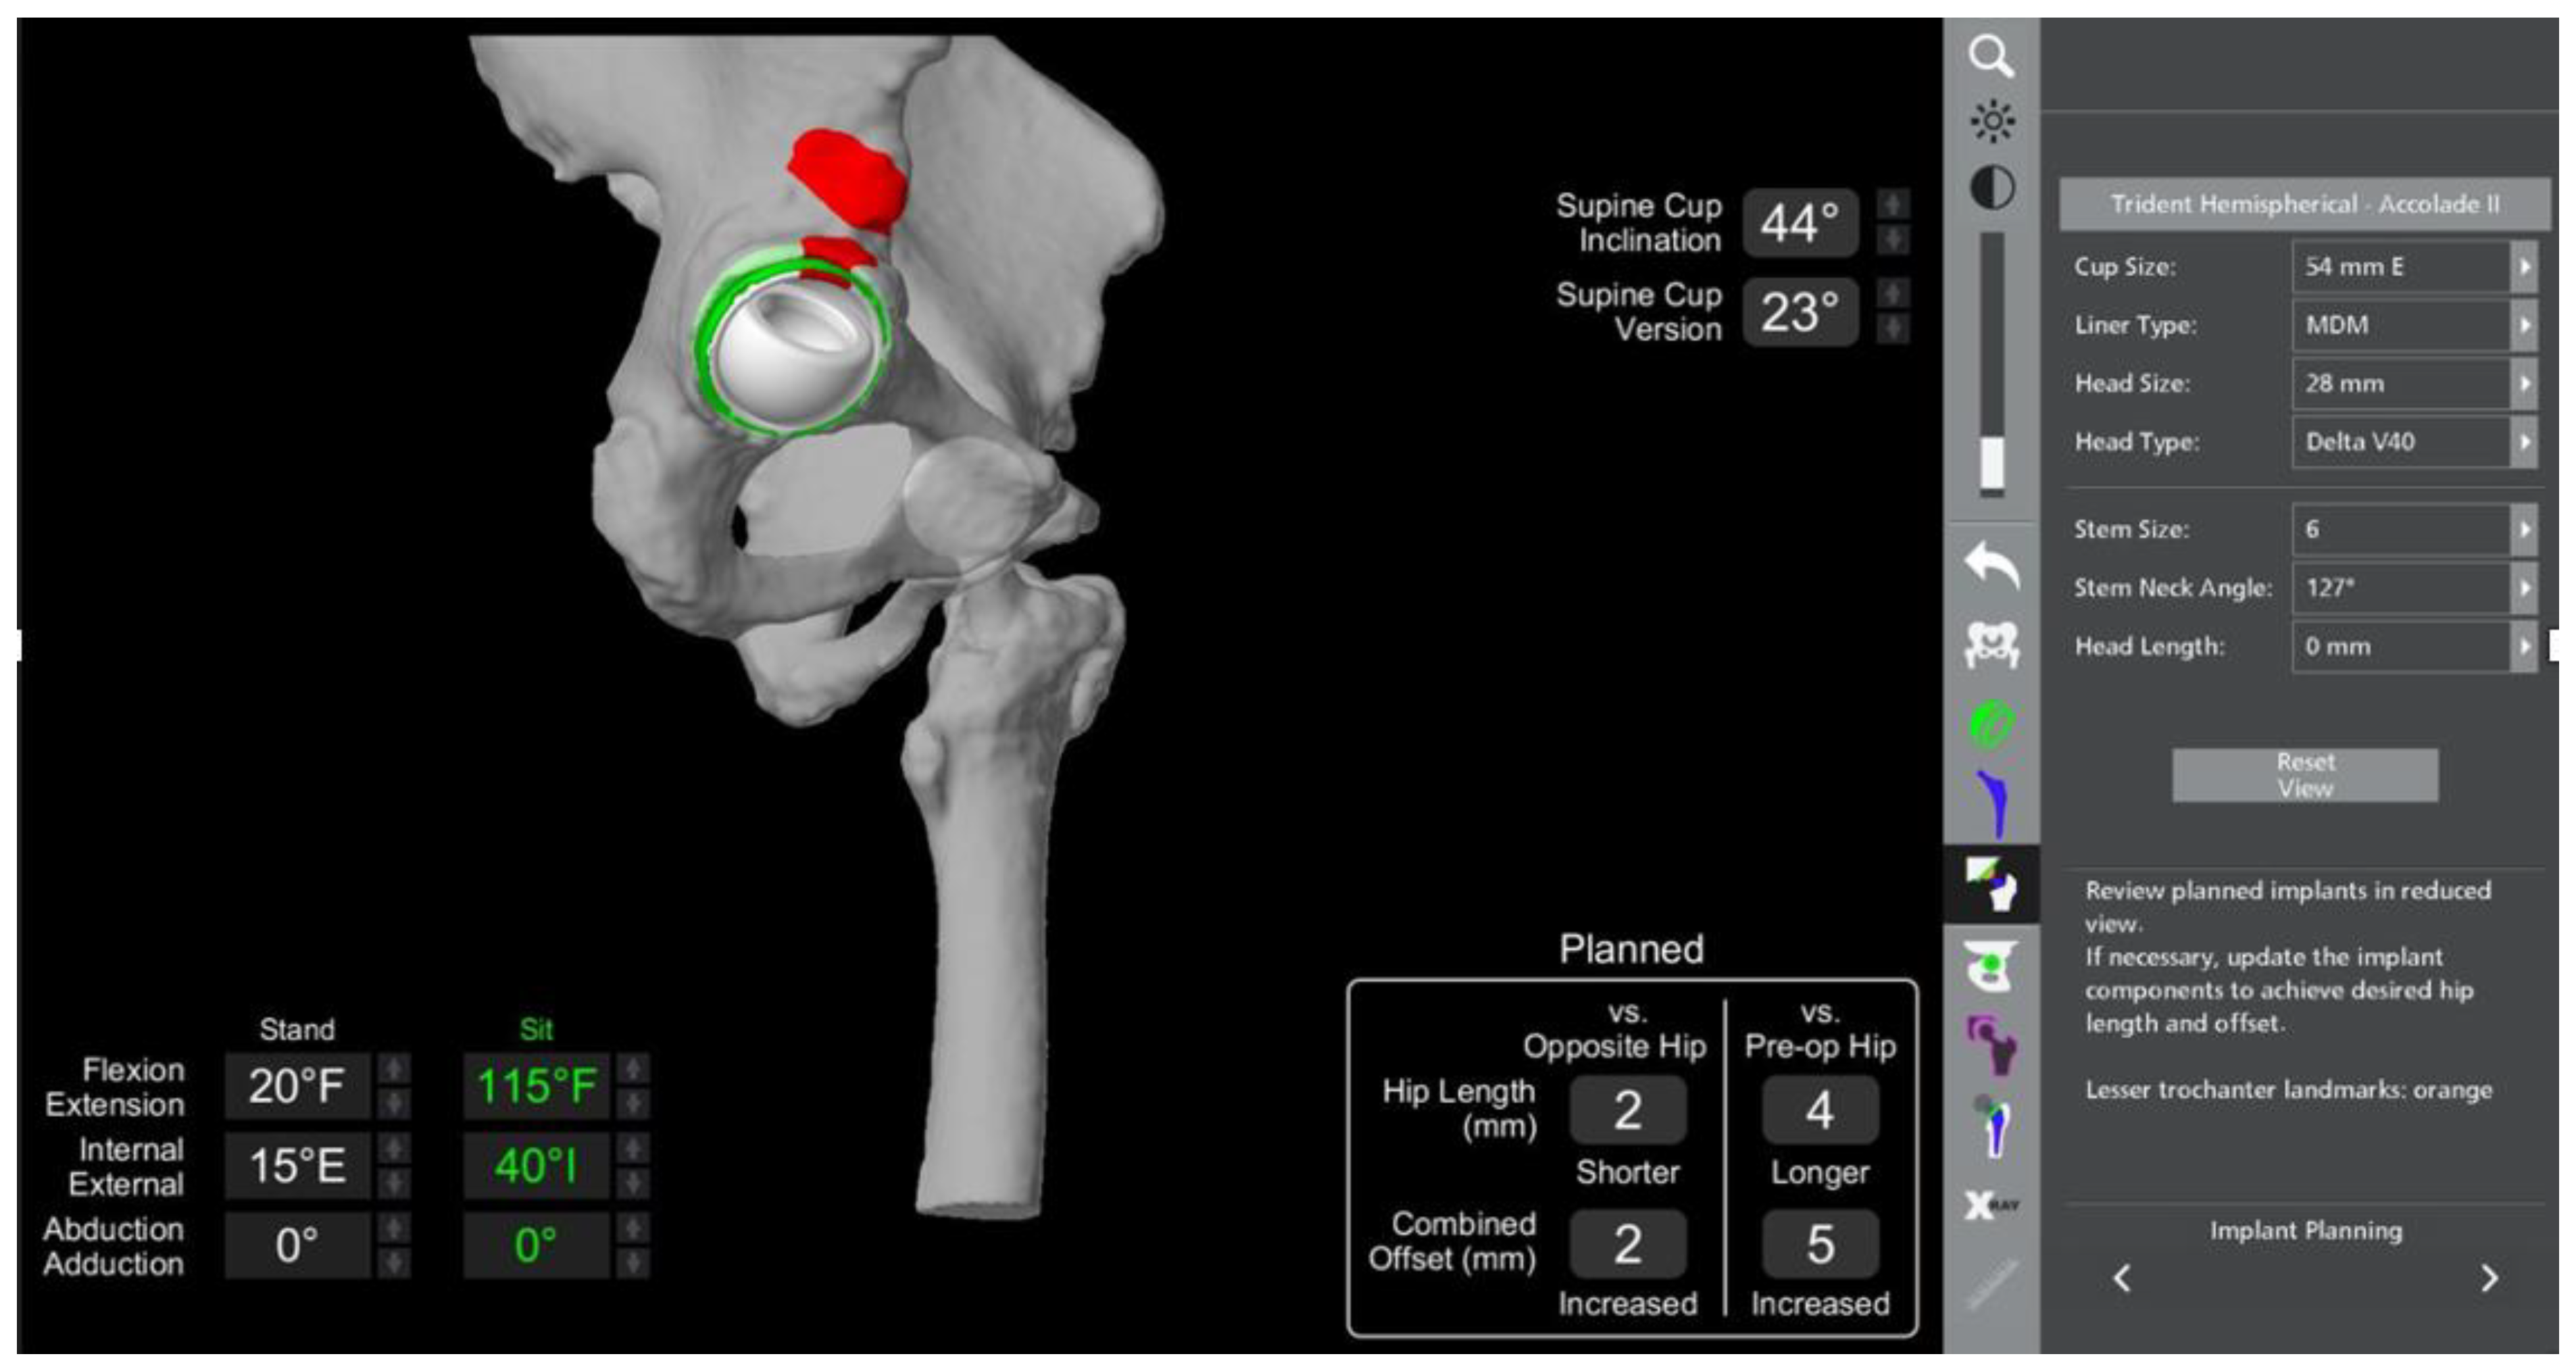

- The robotic software also enables preoperative and intraoperative visualisation of the anticipated postoperative X-rays accounting for any changes to the plan. In addition, the software allows for calculation of changes to the leg length offset compared to the preoperative and contralateral hips. In this case, the leg length was 1 mm longer compared to the opposite hip, and the combined offset was 6 mm increased compared to that preoperatively (Figure 12a,b).